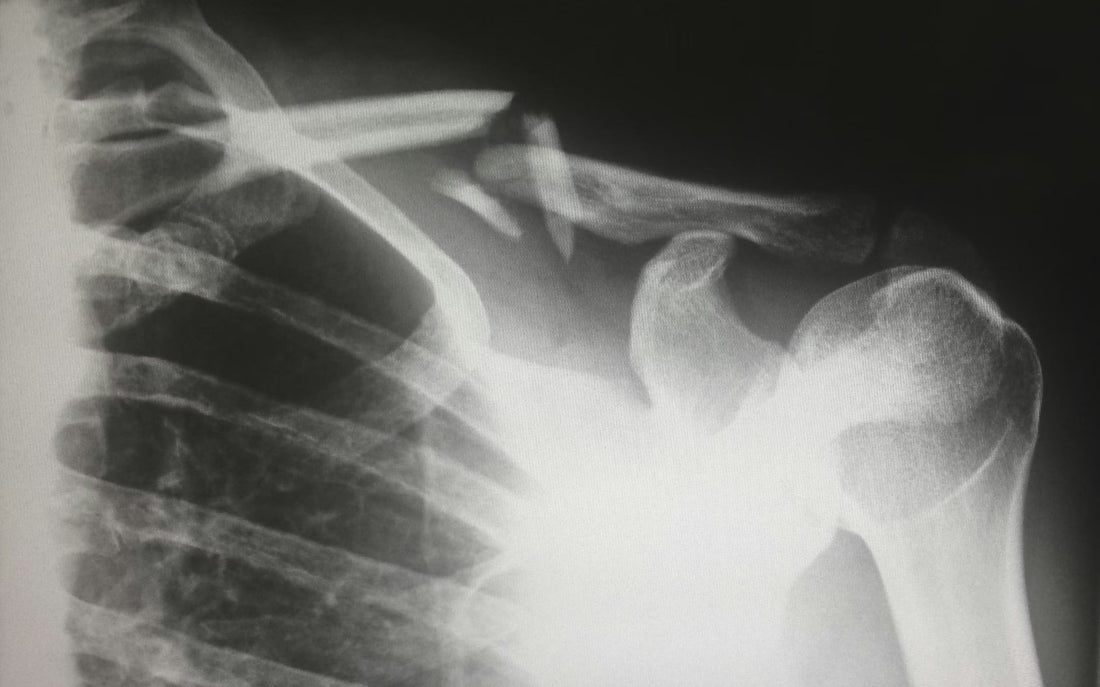

La artroscopía de hombro ha transformado el tratamiento de patologías como el manguito rotador, la inestabilidad glenohumeral y el SLAP (lesión del rodete glenoideo). Sin embargo, para realizarla de forma exitosa y segura, el cirujano necesita contar con un setup quirúrgico completo y bien coordinado. Los componentes esenciales del quirófano para hombro 1. Sistema de visión Una cámara de artroscopía de alta definición (HD o 4K) conectada a una fuente de luz de xenón o LED es el núcleo del procedimiento. Sistemas como el Stryker 1688 4K o el Karl Storz IMAGE1 S ofrecen imágenes nítidas incluso en las zonas más profundas de la articulación glenohumeral. 2. Bomba de artroscopía Mantener la presión de irrigación adecuada dentro del espacio articular es fundamental para la visibilidad. Una bomba como la CONMED 10K permite controlar la presión en tiempo real, reduciendo el riesgo de edema y mejorando el campo visual. 3. Rasurador y radiofrecuencia El rasurador motorizado permite desbridar tejido sinovial y cartílago de manera controlada. La radiofrecuencia, como la Apollo MP90 de Arthrex, es indispensable para hemostasia y ablación de tejidos blandos en espacios reducidos. 4. Instrumental artroscópico Sets de pinzas, cánulas, agujas Scorpion y sistemas de sutura como el FiberWire de Arthrex son fundamentales para la reparación del manguito rotador y la estabilización del hombro. 5. Posicionamiento del paciente La posición en silla de playa o en decúbito lateral requiere accesorios específicos como posicionadores de cabeza y soportes laterales para garantizar acceso óptimo y seguridad del paciente. Consejo práctico Antes de adquirir equipo, verifica la compatibilidad entre los accesorios (cánulas, rasuradores, lentes) y la consola principal que utilizas. En ArtroConfort ofrecemos asesoría técnica sin costo para ayudarte a configurar el setup ideal para tu especialidad.